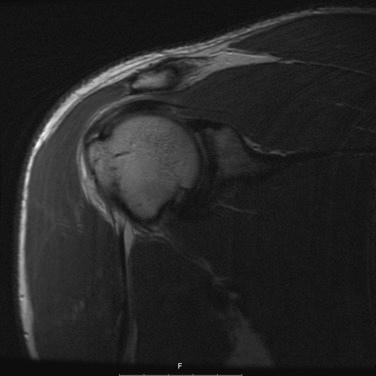

The prevalence of rotator cuff contusions is less defined in the literature. retrospectively reviewed shoulder injuries in collegiate football players. Contusions of the rotator cuff accounted for over half of the shoulder injuries. A direct blow was identified to be responsible for 70% of the contusions noted on MRI ( Fig. 6A.1 )

Fig. 6A.1, MR image of supraspinatus contusion.